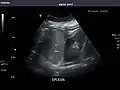

- Spleen

Spleen: Normal in size.